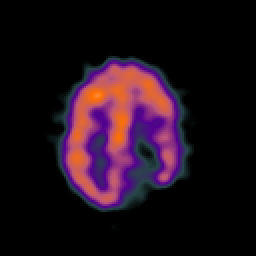

SPECT TC Study #7 -- Slice #40

[Home][Help][Clinical][Tour 1][Tour 2][Tour 3] Slice 40